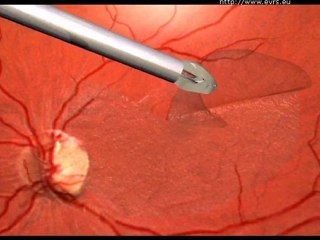

Retinal Detachment

Mr Mahi Muqit PhD FRCOphth is a Consultant Ophthalmologist, Cataract and Vitreoretinal Surgeon at the world famous Moorfields Eye Hospital in London.To more information please visit us .